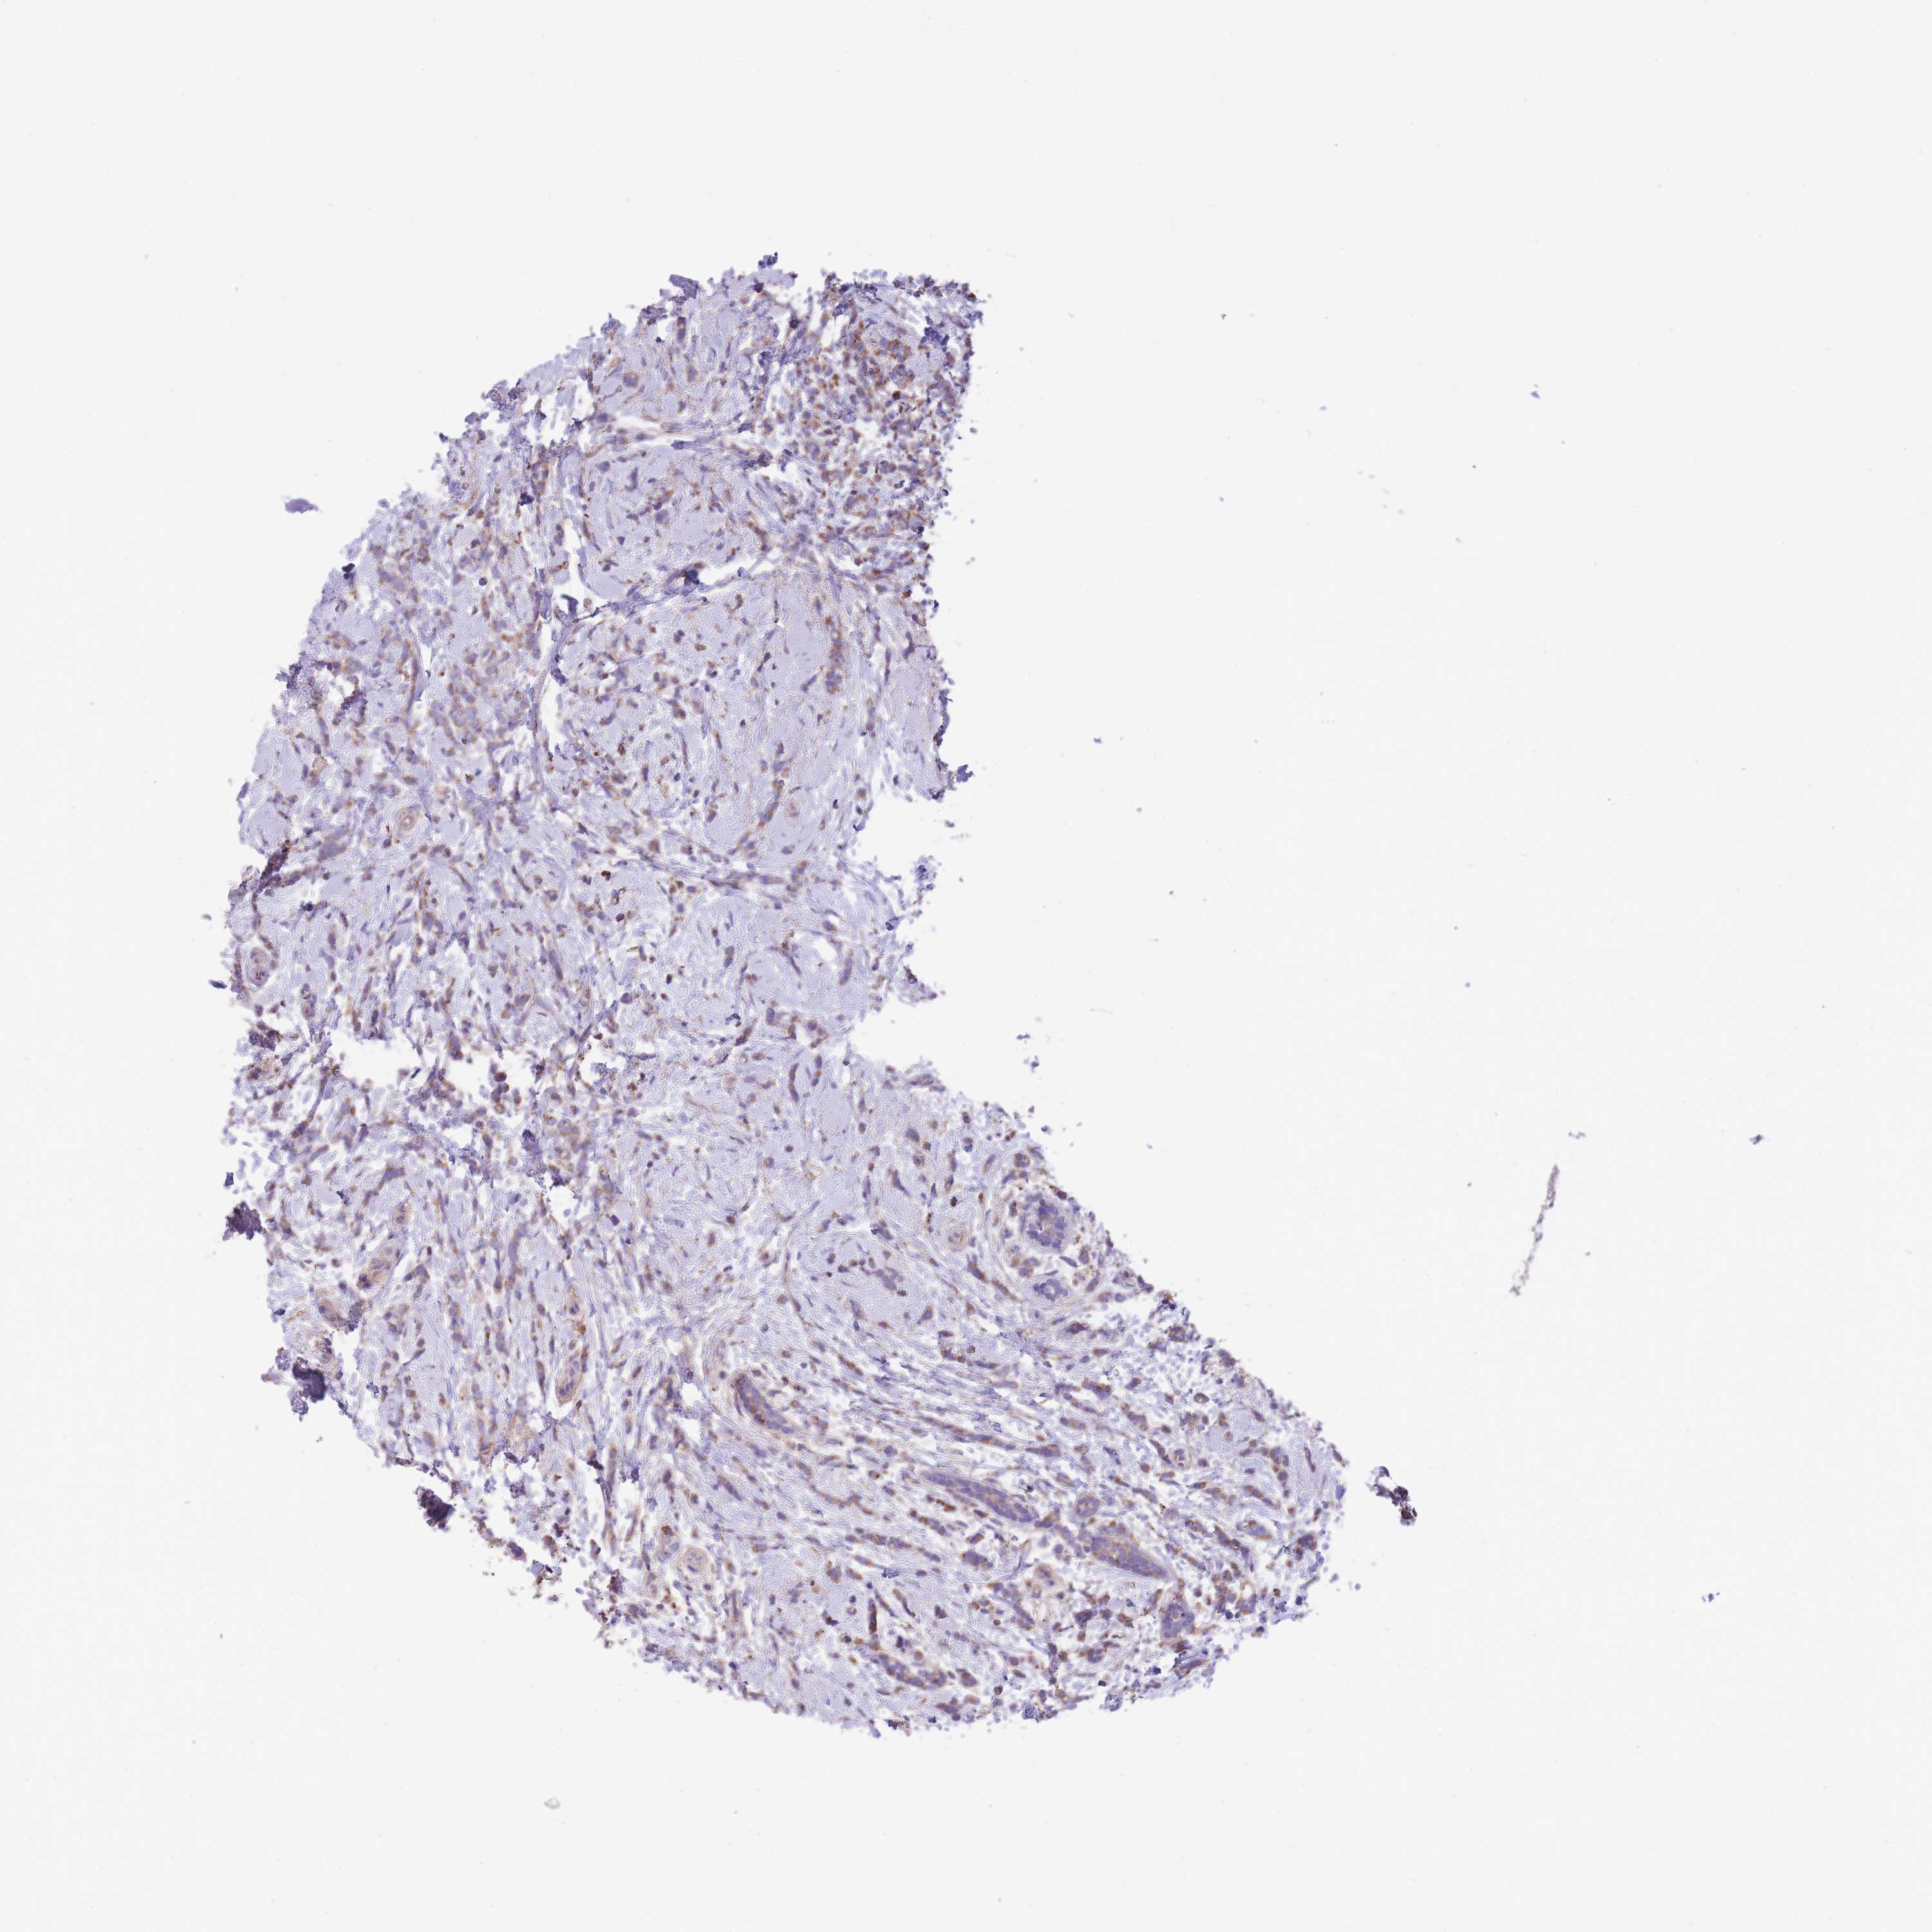

CANCER BREAST CANCER Show tissue menu

BRCA TCGA BRCA VALIDATION PROTEIN EXPRESSION